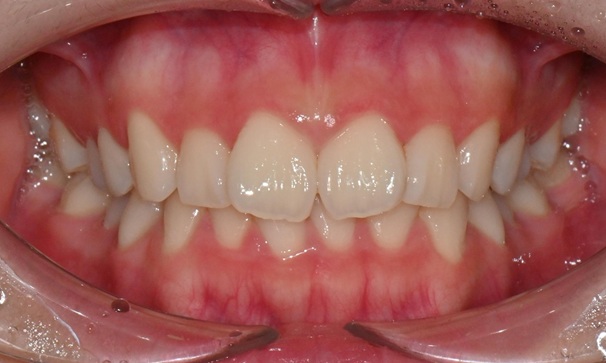

2025.3. 초진 (앞니 경미한 총생과 과개교합) - 연세정원치과

정밀진단 결과 위아래 앞니가 약간 겹쳐 있어 배열이 고르지 않은 상태였으며, 약간의 과개교합이 동반된 상태였습니다. 다만 골격적인 문제나 안모 불균형은 없었고, 측면에서도 돌출감 없이 비교적 안정적인 안모를 유지하고 있었습니다.

이러한 점을 종합적으로 고려해보았을 때 치아 배열의 개선과 교합 조정을 중심으로 한 비발치 교정 치료가 적합한 케이스였습니다. 또한 환자가 고등학생이라는 점, 그리고 학업과 일상 생활에 대한 부담을 최소화하고 싶다는 보호자의 의견을 반영하여, 인비절라인으로 선택하게 되었습니다.

이번 케이스는 인비절라인 Comprehensive로 치료를 진행하였으며, 치아 이동은 과도하지 않게 단계적으로 진행하기 위해 치간삭제를 최소한으로 적용하며 공간을 확보하는 방향으로, 총 33단계의 장치를 통해 치아 이동을 계획하였습니다.